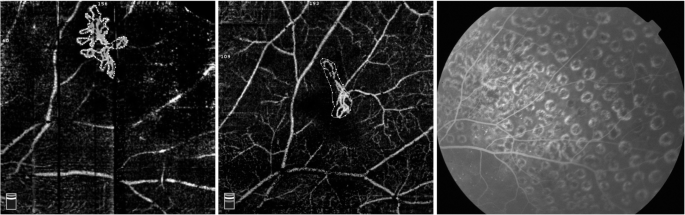

This pilot study has several limitations. First, the small sample size and relatively short follow-up period did not allow for a comprehensive evaluation of NVE changes following PRP treatment. Additional studies to analyse larger datasets are needed to reinforce our results. A second limitation is that the observation of NVE was restricted within a limited field of view and the peripheral NVE could not be visualized. Fortunately, OCTA’s latest technologies, such as extended field imaging (EFI), have solved this problem to a certain extent [15, 16]. Third, OCTA images may also affected by several types of artefacts. Although images with severe artefacts affecting the measurement have been excluded, the potential effect of some artefacts should be carefully evaluated. Some authors have adjusted the image size according to individual axial length [8]. Axial length correction was not performed in this study because all included cases had a refractive error less than ±3.0 D, but this might have an impact on the area calculation of the new vessel area. The NVE area in this study was automatically calculated using the Angiovue software by multiplying the number of pixels for which the decorrelation value was above that of the background. This was dependent on the image quality and might influence the repeatability of measurements in some cases. The leakage of new vessels could not be identified with OCTA as it can with FFA; thus, the activity of the NV could not be directly evaluated, and the presence of residual vessels on OCTA may or may not correlate with activity or risk of vision loss. Therefore, in cases with persistent NV on OCTA, FFA is warranted to assess its activity, and the prognosis of such blood vessels needs further investigation. In one of our cases, a shrinking NVE was present on OCTA images of 1 year after PRP, but no fluorescein leakage was observed on FFA at the same time (Fig. 3), suggesting that the endothelial cells of these residual blood vessels may have improved or even achieved normal function. However, the prognosis of such blood vessels is still unclear and needs further observation.

Neovascularization at baseline OCTA with a select area of 0.998 mm2 (highlighted) and a flow area of 0.653 mm2 (left); OCTA still showed an abnormal vascular shape at an interval of 1 year after PRP, with a select area of 0.675 mm2 (highlighted) and a flow area of 0.272 mm2 (middle), and no evidence of fluorescein leakage was seen on the FFA (right)